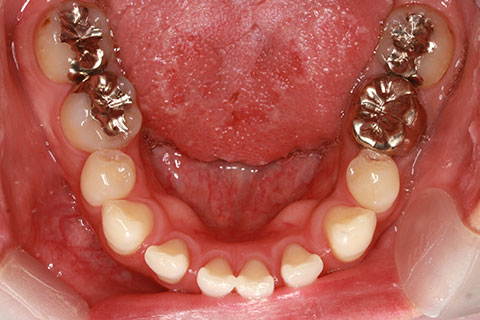

ハーフリンガル矯正3:上の歯のみ舌側矯正で治療(矯正期間24ヶ月)

治療前

治療中(開始直後)

治療中(開始半年後)

治療後

- 年齢・性別

- 25歳女性

- 治療期間

- 2年0ヶ月

- 抜歯

- 上下4番抜歯

- 治療費

- 110万円

- 治療内容

- 施術の副作用(リスク)

- 表側矯正と比較して、力学的な操作性が複雑なため、ボーイングエフェクトを起こしやすい。